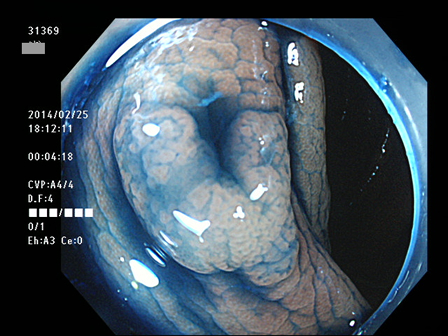

上記100名より抽出した平坦・陥凹型腺腫(=癌化の危険が高いが見落としやすい病変)の内視鏡写真

31369 31370 31371 31372 31375 31379 31381 31384 31385 31387 31389 31390